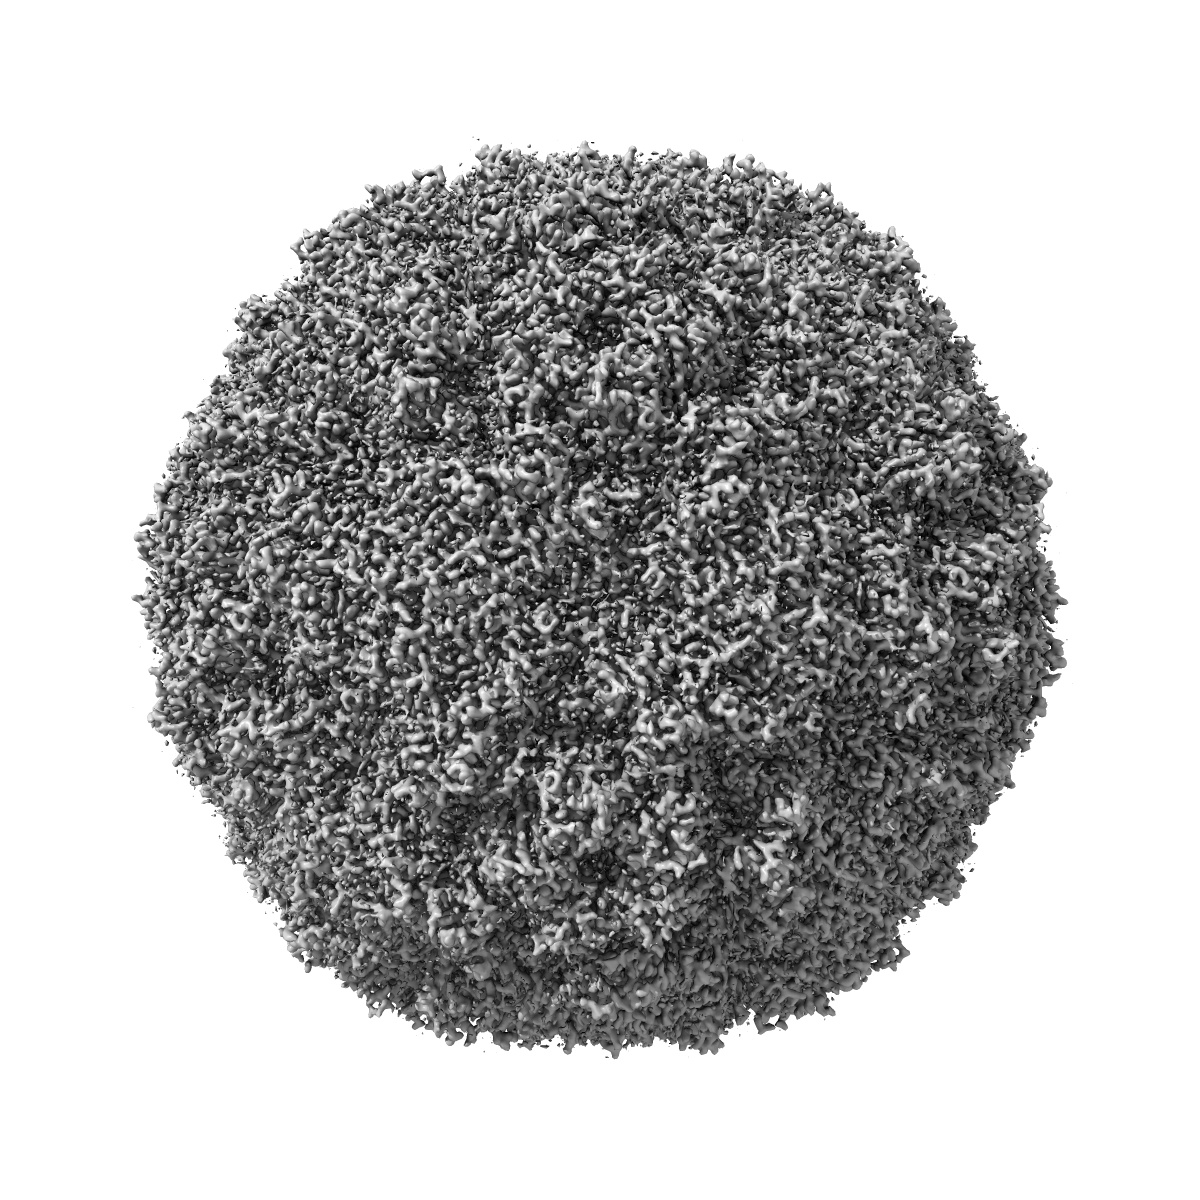

EVA71 E096A native particle

Single-particle2.5 Å

Enterovirus A71

Mechanism of enterovirus VP0 maturation cleavage based on the structure of a stabilised assembly intermediate.